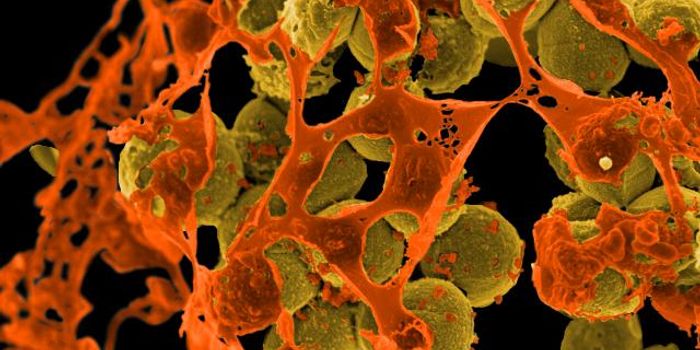

AUG 20, 2016Clinical & Molecular DXCan the staph superbug, also known as MRSA, be brought down by salt? Scientists finally expose a key weakness in these b ...

MAR 11, 2015MicrobiologyHouseholds can serve as a reservoir for transmitting methicillin-resistant Staphylococcus aureus (MRSA), according to a ...